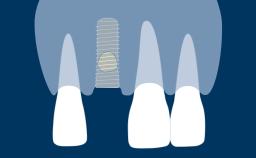

Desenho do Retalho

Vários fatores influenciam o sucesso do tratamento com implantes. Isso inclui requisitos básicos para o aspecto cirúrgico da terapia com implantes. Este módulo se concentrará nos princípios básicos do desenho do retalho para cirurgia oral em geral e para procedimentos cirúrgicos de implante. O objetivo é garantir que a cirurgia possa ser realizada o mais atraumaticamente possível, com visibilidade e acesso adequados à área cirúrgica.

- descrever os princípios desenho do retalho

- descrever os princípios desenho do retalho para cirurgia de implante

- descrever os princípios desenho do retalho para cirurgia de implante